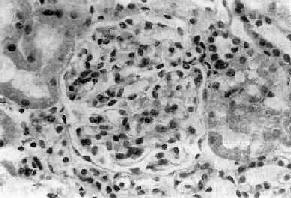

图12-10 弥漫性系膜增生性肾小球肾炎

肾小球系膜区略增宽,系膜细胞数量增多

主要病变为肾小球系膜细胞和基质增生,系膜区增宽(图12-10,图12-11)。毛细血管壁无明显变化,管腔通畅。系膜内可有少数单核细胞和中性粒细胞浸润。病变严重者可引起系膜硬化。